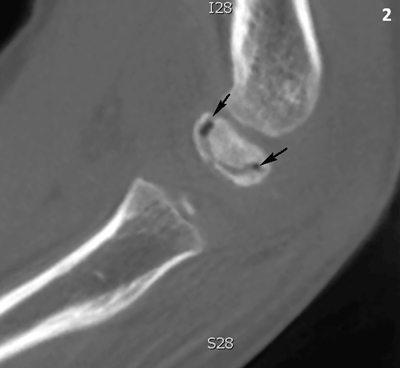

A seven-year-old boy presented with pain in his left elbow with a subtle swelling following a fall. There was a limited range of motion, mostly an extension deficit of the elbow. Conventional radiography (CR) of the left elbow (Figure 1) revealed joint effusion (asterisk) and irregular delineation of the articular contour of the capitellum with a radiolucent line in the subchondral bone (black arrows). There was also faint sclerosis of the capitellum (white arrows). Subsequent cone beam computed tomography (CT) (Figure 2) depicted a crescent-shaped subchondral vacuum phenomenon in the capitellum (black arrows). The diagnosis of Panner’s disease was made and the patient was treated conservatively, with rest, temporary immobilization and subsequent remobilization. The clinical follow-up was uneventful.

Cone beam CT of the right elbow, sagittal reformatted image. The capitellum has an increased density. There is a subchondral crescent-shaped vacuum phenomenon (black arrows).